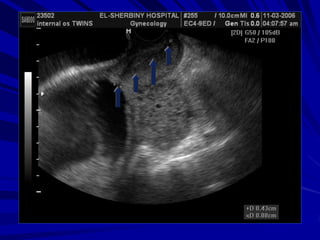

the progressive shortening

detected by serial sonar,

funneling (width and length),

v-shaped lower uterine segment

and dynamic cervical changes

with fundal or suprapubic

pressure.